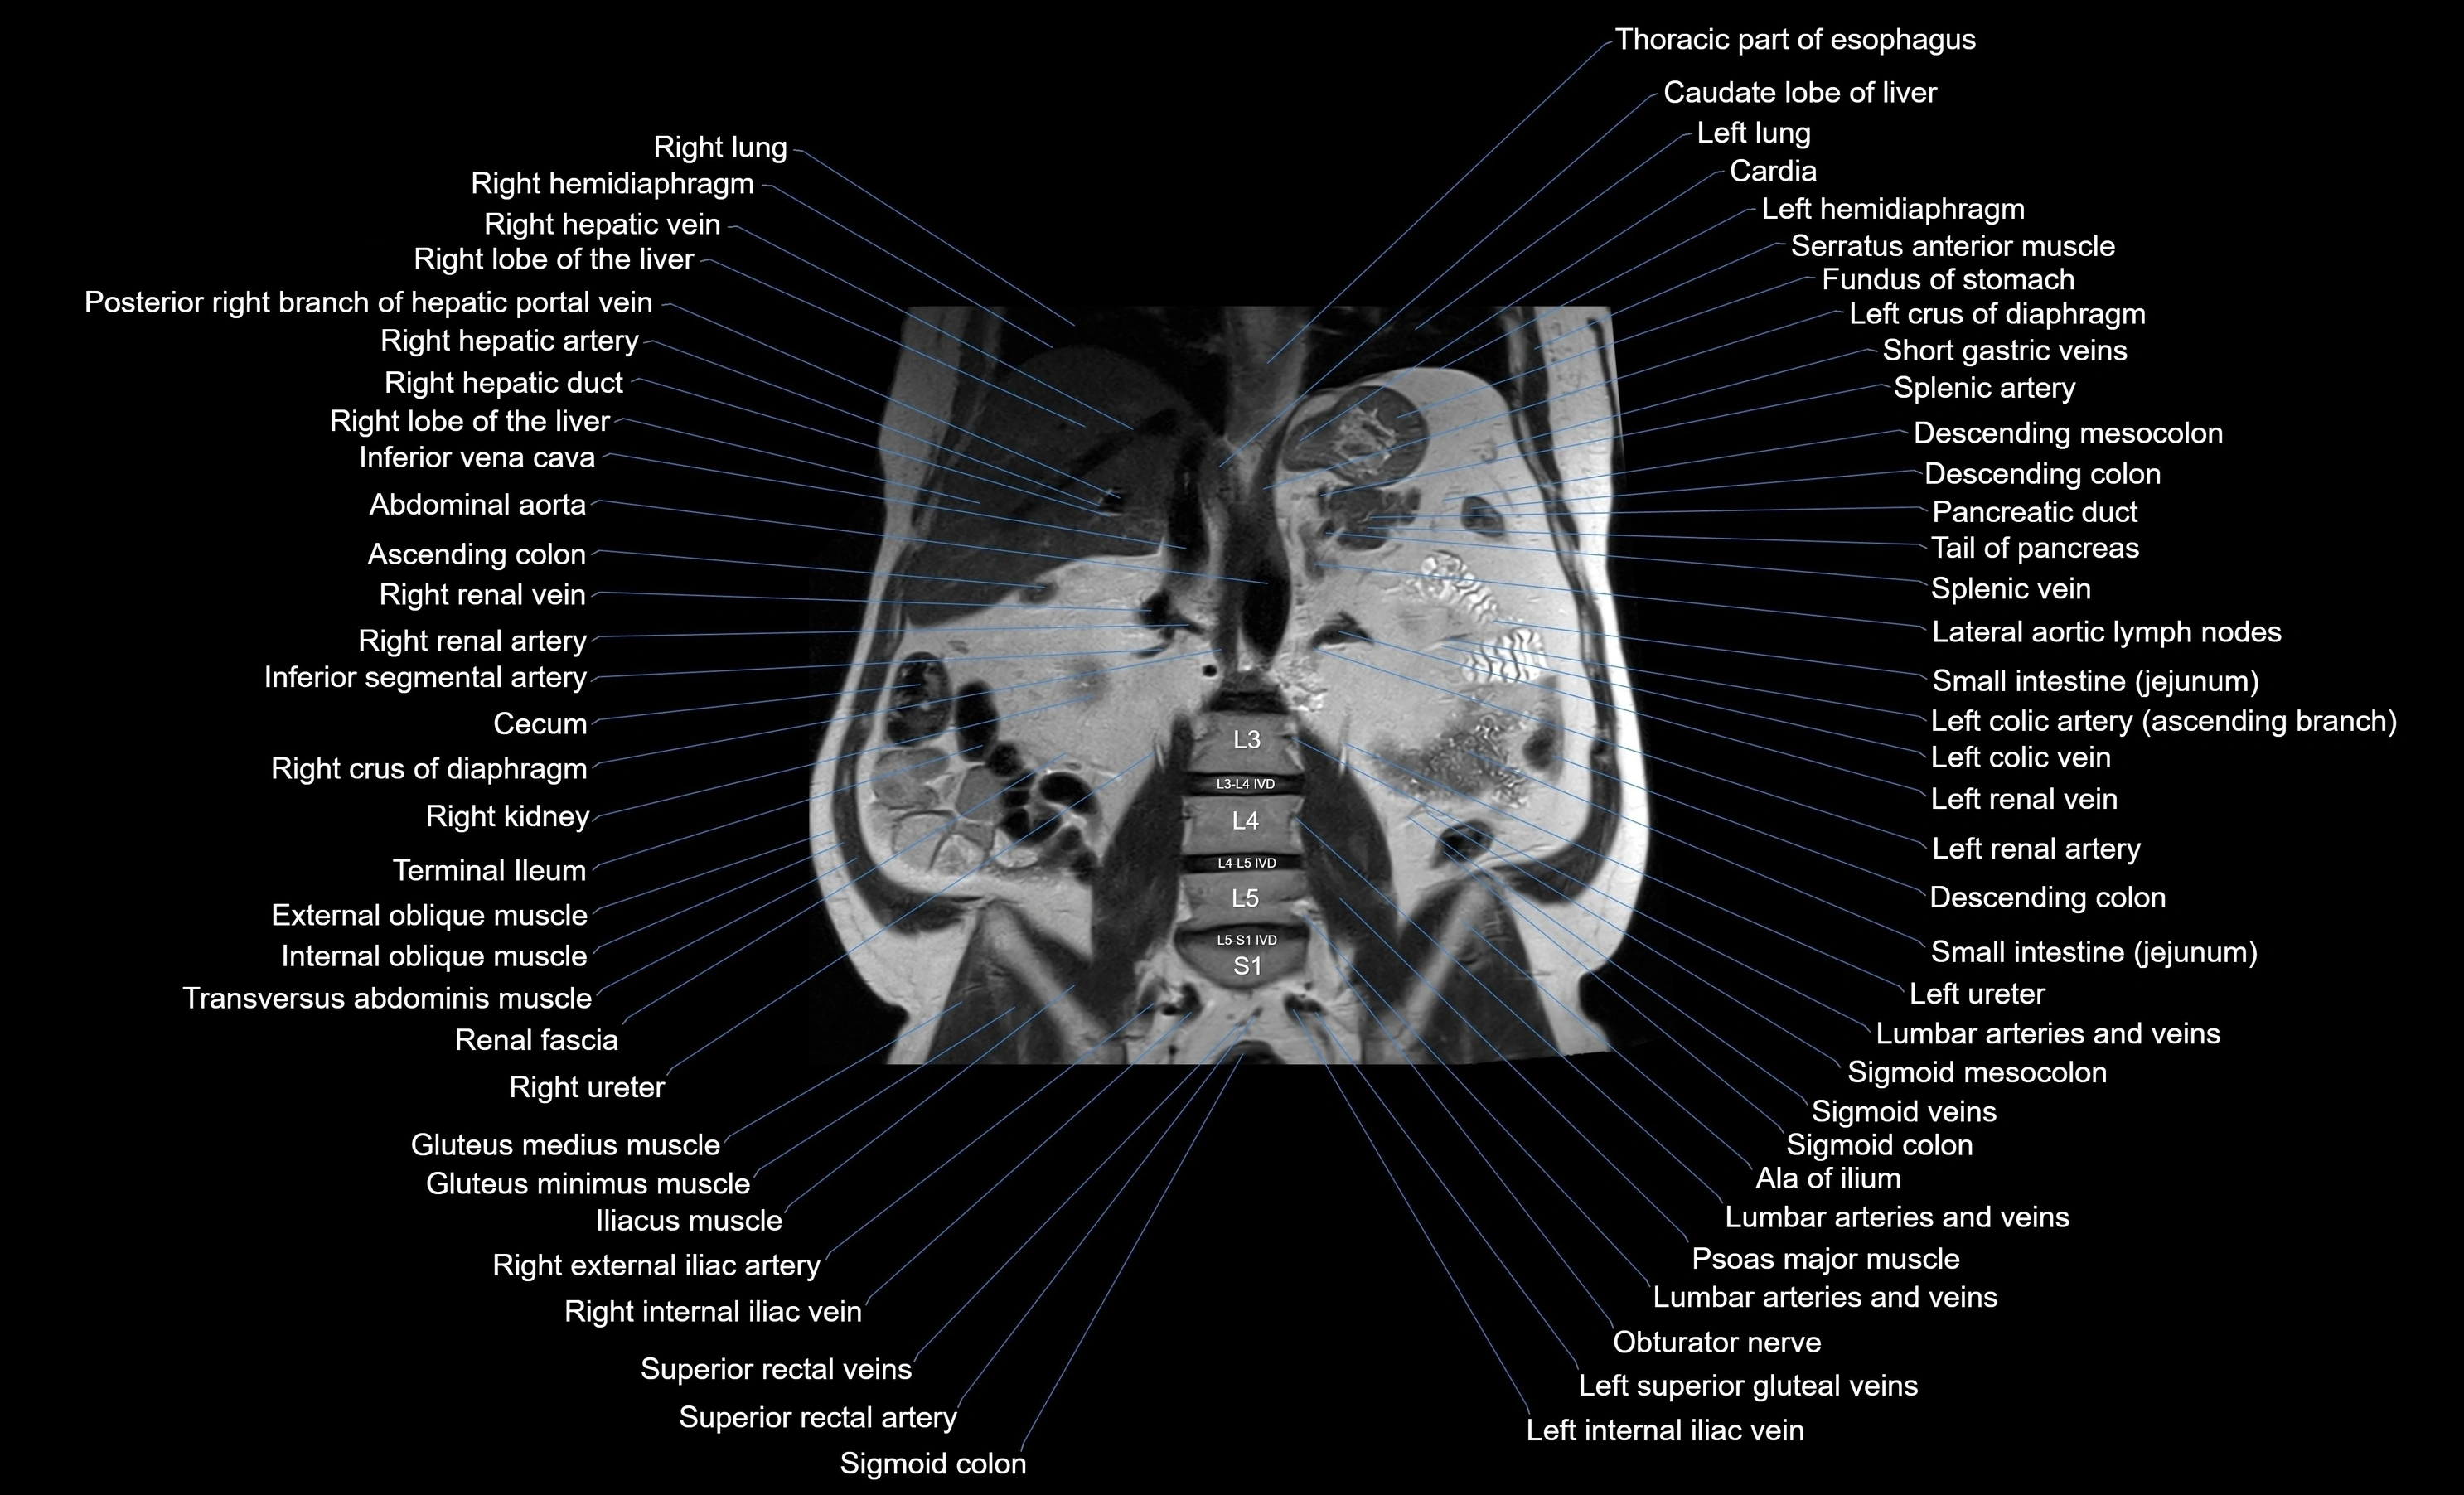

- Abdominal aorta

- Descending colon

- Ascending colon

- Cecum

- Inferior vena cava

- Left kidney

- Right kidney

- Left renal artery

- Left renal vein

- Left ureter

- Splenic artery

- Spleen

- Tail of pancreas

- Pancreatic duct

- Inferior mesenteric artery (IMA)

- Left colic artery